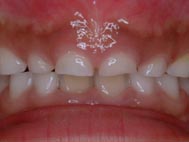

3ヶ月後、まだ乳前歯は抜けておらず、右上の乳歯が真ん中に寄ってきました。真ん中にあった隙間もなくなり、歯と歯ぐきの間に隙間ができてきました。レントゲンでは永久歯が乳歯を下から突き上げていることが確認できます。そのことが原因で、右上の乳歯の位置が変わってきたと思われます。この様な状態では乳歯を抜いてあげる方が良いでしょうね。もちろん、乳歯の根は充分に溶けていますので自分自身かご家族の誰かが抜くこともできます。